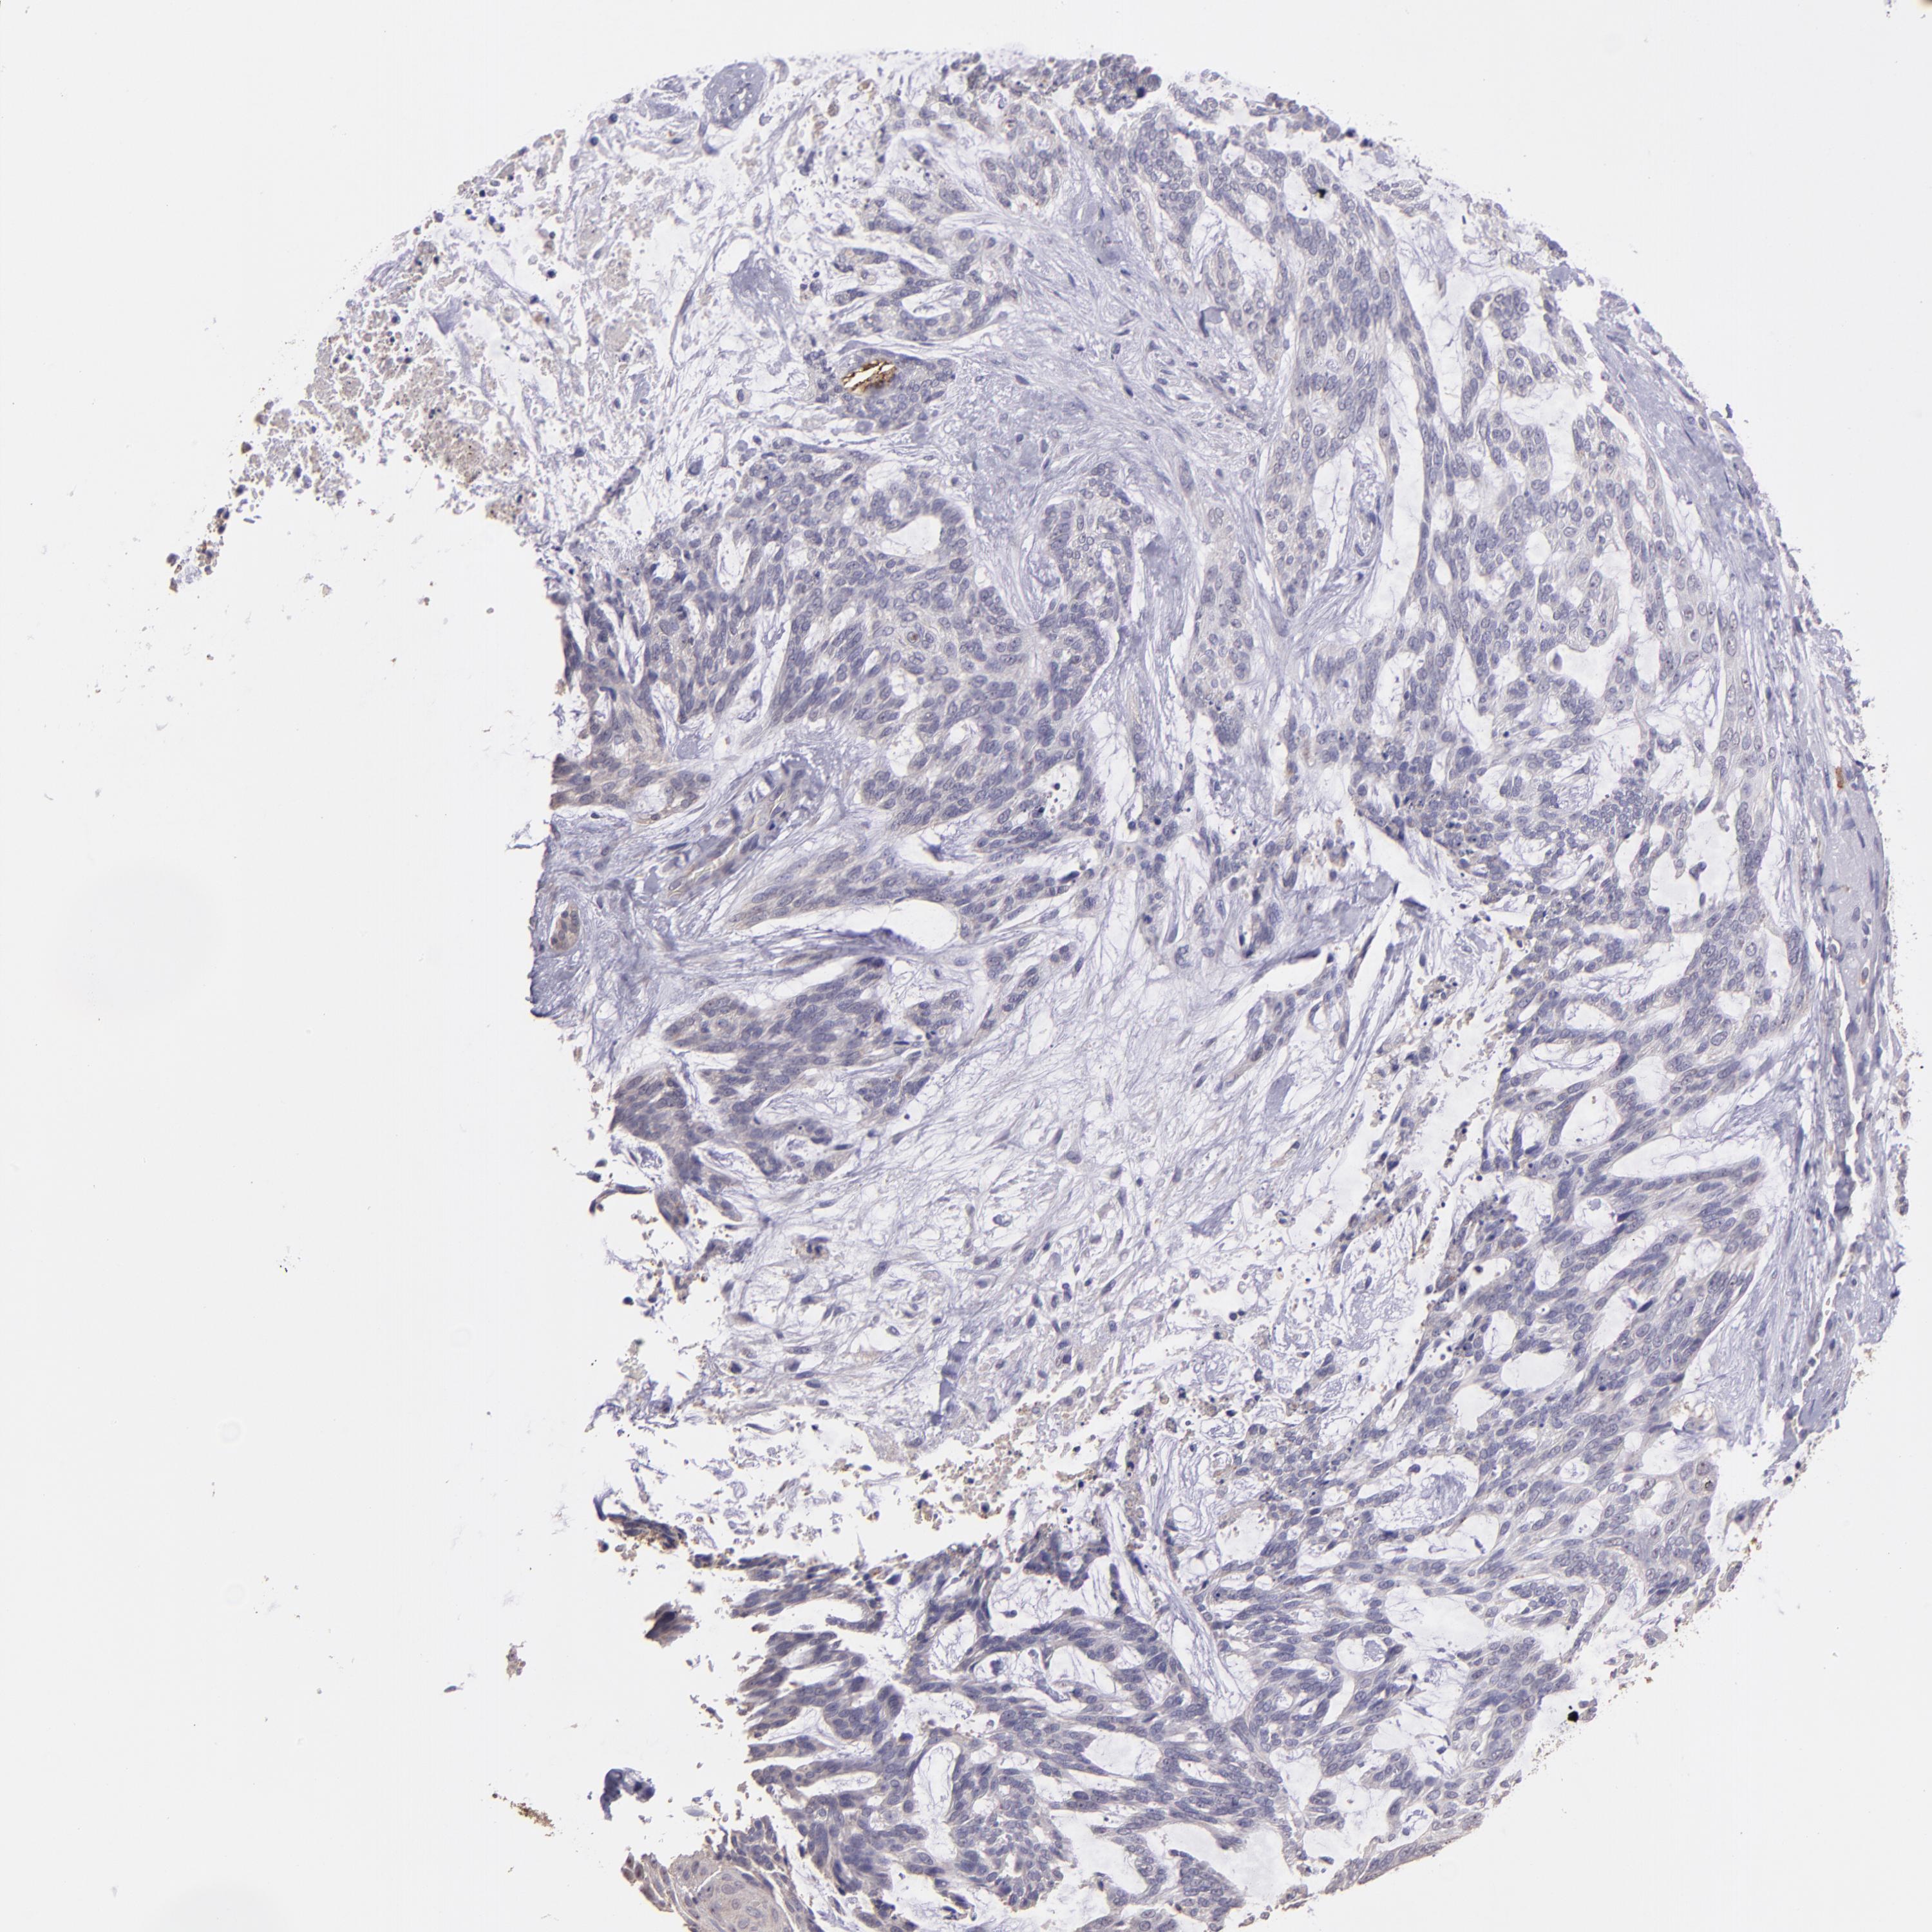

SKIN CANCER - Protein expressioni

A mouse-over function shows sample information and annotation data. Click on an image to view it in a full screen mode. Samples can be filtered based on level of antibody staining by selecting one or several of the following categories: high, medium, low and not detected. The assay and annotation is described here.

Each image is clickable and will lead to virtual microscopy that enables deeper exploration of all samples and also displays staining intensity scores, fraction scores and subcellular localization as well as patient and tissue information for each sample.

Antibody CAB016724

Squamous cell carcinoma, metastatic, NOS